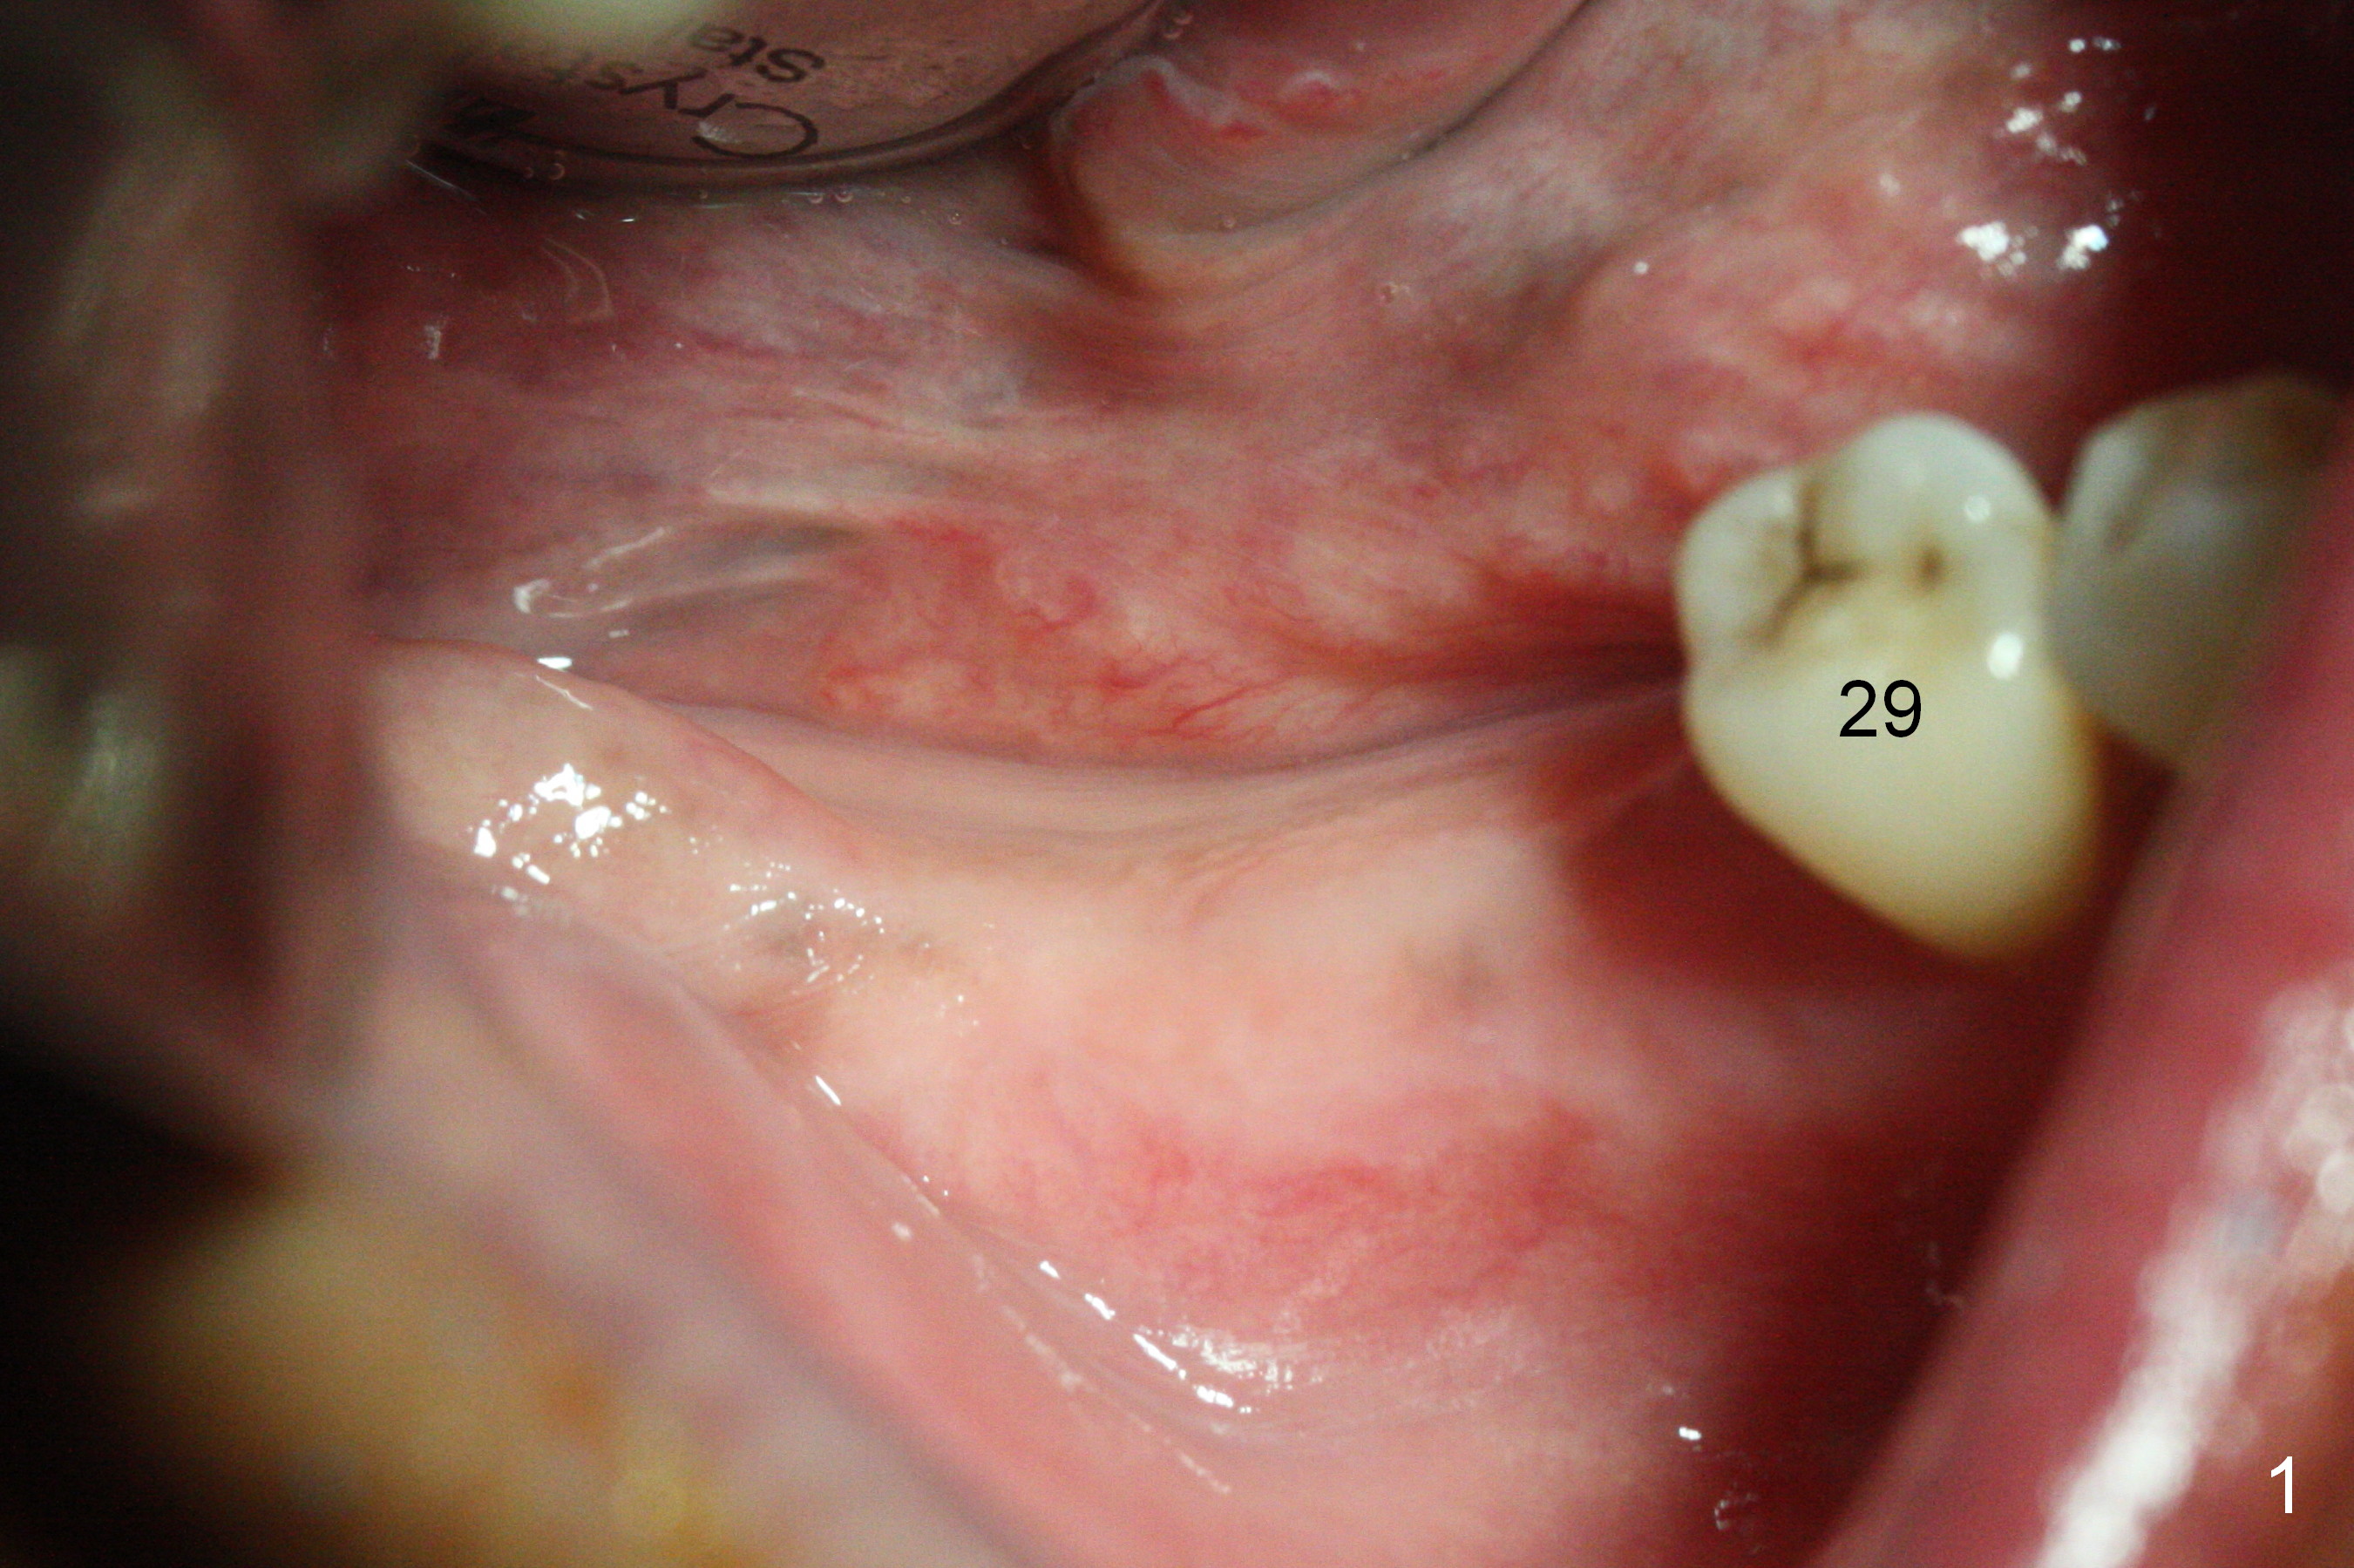

The supraerupted tooth #2 is adjusted using the lower right surgical stent. Osteotomies are initiated by using starter drill through surgical stent over the ridge (Fig.1) prior to incision. The initial depths are 10 and 12 mm at the sites of #31 and 30, respectively (Fig.2). The new sensor with the existing sensor holder cannot reach the deep portion of the lingual vestibule (Fig.2,3). Without the sensor holder, the #2 sensor with rounded corners has no problem showing the Inferior Alveolar Canal (Fig.4 red dashed line). The two implants (5x12 and 5x14 mm, Fig.5) are placed with >50 Ncm. Cemented abutments are immediately placed (6.8x4(2) and 6.8x4(3) mm) to reduce suture tension (after autogenous bone graft and collagen dressing) and hold periodontal dressing in place. The wound does not heal completely 15 days postop (Fig.6). The patient reveals that he smokes 1/2 pack per day. There is crestal bone resorption 4 months postop (Fig.7 *). It appears that for smokers, implants should be smaller, placed deeper and buried. In addition, his oral hygiene is not good.